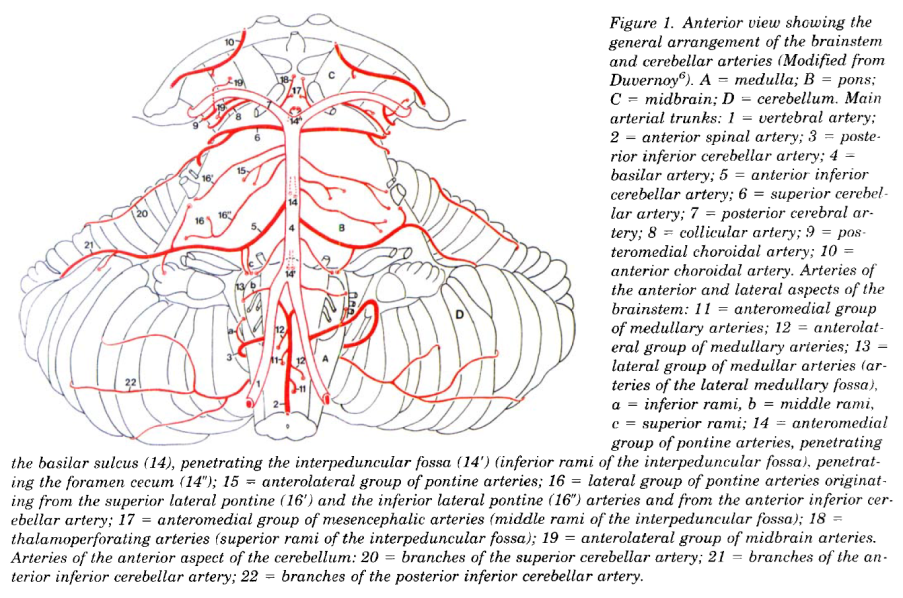

Cerebral vascular territories

Brainstem